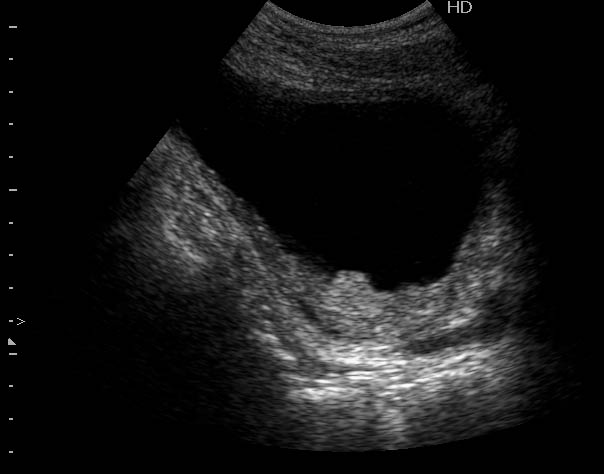

вариант течения о.цистита

а это специальный цистит без типичных узи-признаков, за исключением одного - взвесь. толщина стенки мочевого указана неспроста. а клиника и лаборатория - по полной программе.

Богу богово, кесарю - кесарево (я про анализы и клинические данные). На сонограммах неубедительно продемонстрирован осадок да и стенки м.п. не утолщены.

пы.сы. я ее смотрела на 7й или 8й день заболевания, до этого несколько узи в городской больнице. цистоскопия - отечные устья, локально вокруг устьев - изменения слизистой. вели как цистит. жалобы ушли на 3й день.

зато какое наполнение! а осадок убедительный! а же не 7-кой смотрела!На сонограммах неубедительно продемонстрирован осадок да и стенки м.п. не утолщены.

Продольное сканирование мочевого пузыря После легкой перкуссии мочевого пузыря